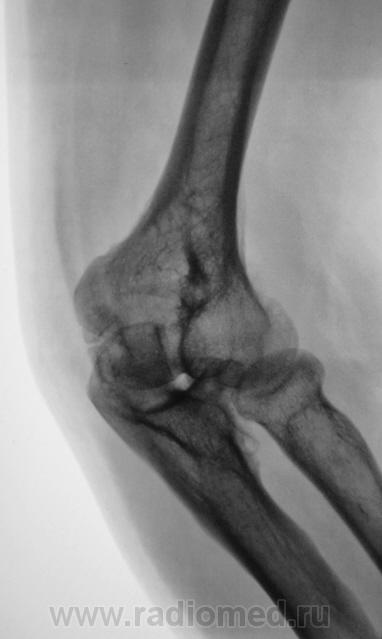

Пациент направлен на рентгенографию локтевого сустава. Была травма или не была не помнит. Пациент весьма пьющий, направлен хирургом с диагнозом "перелом". Рука в локтевом суставе полность не разгибается.

Ваше мнение уважаемые коллеги?

Наверно, застарелый перелом в области блока плечевой кости. Не понятен периостит.